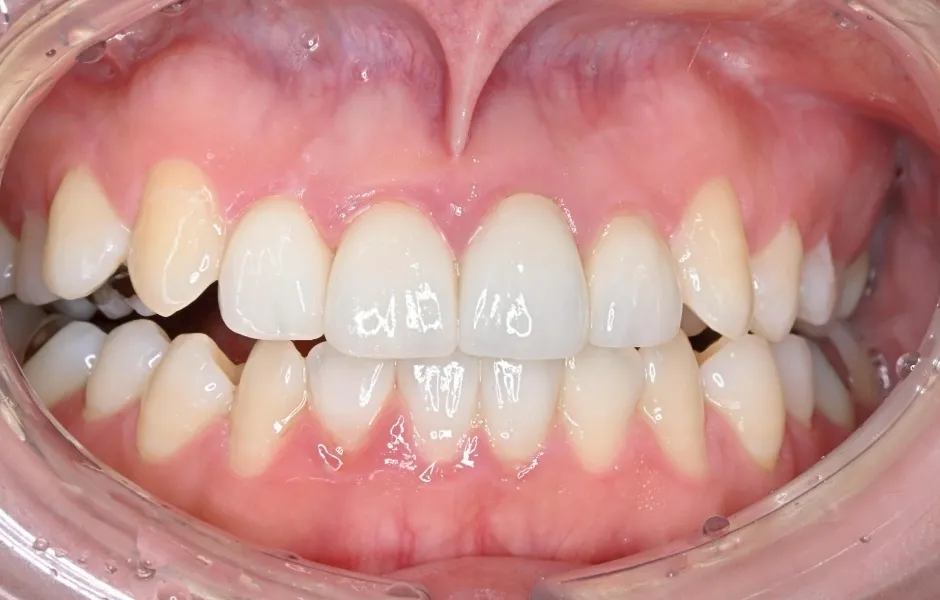

全顎治療・咬合治療

(歯がボロボロ)虫歯や歯周病が悪化して、歯を失っている・ボロボロのまま放置すると、機能性と審美性に影響がでます。お口のトラブルを改善できるよう、さまざまな治療をご提案します。

全顎治療・咬合治療(歯がボロボロ) -